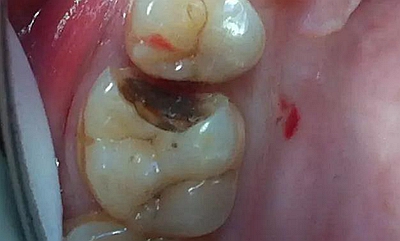

病例一 女性,20歲,大學(xué)生,要求補(bǔ)牙,檢查口內(nèi)可見A6大面積缺損,近中牙齦息肉,拍X片,根管充填物略差,但根周未見明顯陰影,口內(nèi)檢查無(wú)叩痛。建議患者冠延長(zhǎng)手術(shù)+高嵌體修復(fù)。

患牙遠(yuǎn)中邊緣嵴完整,強(qiáng)度沒(méi)有降低,故擬保留遠(yuǎn)中邊緣嵴,高嵌體修復(fù)。首先去除腐質(zhì)及原墊底材料,流體樹脂+3M Z350XT樹脂墊底。局麻下行冠延長(zhǎng)手術(shù)。在此需要提及個(gè)人的一個(gè)觀點(diǎn)。冠延長(zhǎng)手術(shù)原則上要求3-6個(gè)月以上才能永久修復(fù)。但是個(gè)人喜歡后牙肩臺(tái)建立在齦上,所以修復(fù)后的修復(fù)體邊緣位于牙齦上方1mm,對(duì)牙周的愈合影響較?。ㄈ绻麨辇l下邊緣則要慎重),故該患者術(shù)中按照齦上邊緣的設(shè)計(jì)進(jìn)行冠延長(zhǎng)手術(shù)。以下為術(shù)中: